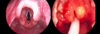

How does AOM present on examination?

Always check the ears and throat of unwell children

• Bulging red TM

• May be yellow or cloudy

• Loss of light reflex